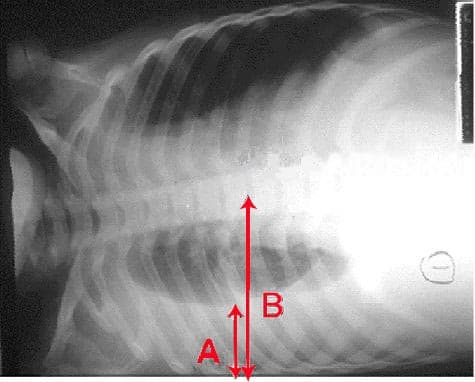

Pleurisy, also known as pleuritis, is inflammation of the membranes that surround the lungs and line the chest cavity (pleurae). This can result in a sharp chest pain while breathing. Occasionally the pain may be a constant dull ache. Other symptoms may include shortness of breath, cough, fever, or weight loss, depending on the underlying cause. Pleurisy can be caused by a variety of conditions, including viral or bacterial infections, autoimmune disorders, and pulmonary embolism. The most common cause is a viral infection. Other causes include bacterial infection, pneumonia, pulmonary embolism, autoimmune disorders, lung cancer, following heart surgery, pancreatitis and asbestosis. Occasionally the cause remains unknown. The underlying mechanism involves the rubbing together of the pleurae instead of smooth gliding. Other conditions that can produce similar symptoms include pericarditis, heart attack, cholecystitis, pulmonary embolism, and pneumothorax. Diagnostic testing may include a chest X-ray, electrocardiogram (ECG), and blood tests. Treatment depends on the underlying cause. Paracetamol (acetaminophen) and ibuprofen may be used to decrease pain. Incentive spirometry may be recommended to encourage larger breaths. About one million people are affected in the United States each year. Descriptions of the condition date from at least as early as 400 BC by Hippocrates. The defining symptom of pleurisy is a sudden sharp, stabbing, burning or dull pain in the right or left side of the chest during breathing, especially when one inhales and exhales. It feels worse with deep breathing, coughing, sneezing, or laughing. The pain may stay in one place, or it may spread to the shoulder or back. Sometimes, it becomes a fairly constant dull ache. Depending on its cause, pleuritic chest pain may be accompanied by other symptoms: Dry cough Fever and chills Rapid, shallow breathing Shortness of breath Fast heart rate Sore throat followed by pain and swelling in the joints Pleurisy is often associated with complications that affect the pleural space.